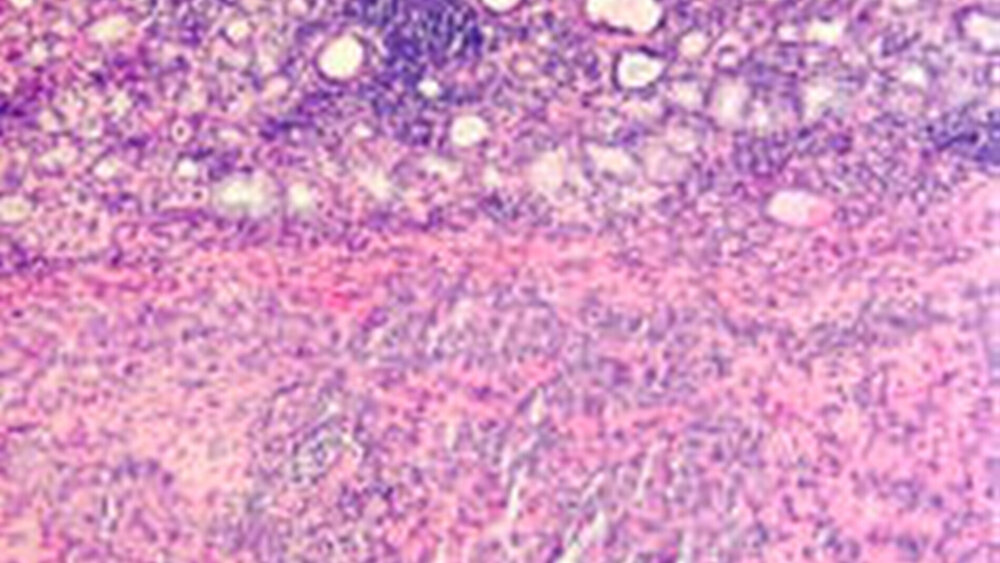

Die endgültige histopathologische Untersuchung, Dr. Stephan Schwarz, Institut für Pathologie der Universität Regensburg, bestätigte die vollständige Entfernung eines 0,7 Zentimeter großen pleomorphen Adenoms bestehend aus Epithelnestern und dazwischenliegendem Stroma mit zum Teil myxoiden und chondroiden Anteilen (Abbildungen 3a und b).

Am Gaumen ist der Tumor gekennzeichnet durch ein langsames, zumeist schmerzloses Wachstum und imponiert durch palpatorisch eher harte, unverschiebliche und gelegentlich bläulich schimmernde Auftreibungen. Wiederholte Reibung kann wie im gezeigten Falle zu Drucknekrosen der Schleimhaut führen [Ehrenfeld und Prein, 2002; Cawson et al., 1997]. Während das pleomorphe Adenom der großen Speicheldrüsen zumeist von einer bindegewebigen Kapsel umgeben ist, fehlt diese oftmals bei den Neubildungen am Gaumen oder ist, wie im aktuellen klinischen Fall, auf eine zarte Bindegewebslamelle beschränkt (Abbildung 3b). Gelegentlich ist an dieser Stelle Periost, in seltenen Fällen auch Knochen in das Geschehen mit involviert [Clauser et al., 2004].

Histologisch imponieren pleomorphe Adenome durch ihre strukturelle Pleomorphie. Es finden sich epitheliale und myoepitheliale Zellen gemischt mit mesenchymalen mukoiden, myxoiden und chondroiden Elementen, daher auch der Name Mischtumor [Ehrenfeld und Prein, 2002]. Obwohl es sich beim pleomorphen Adenom um einen gutartigen Tumor handelt, besitzt es einige therapierelevante Besonderheiten. Beschrieben ist das gelegentliche Auftreten von Lokalrezidiven (Rezidivquote < 5 Prozent) bei inadäquater Tumorentfernung beziehungsweise reiner Enukleation des Tumors und einer damit verbundenen intraoperativen Implantation von Tumorgewebe in umgebendes Weichgewebe [Sexauer-Gerlach und Strutz, 2001]. Einen ganz wesentlichen Gesichtspunkt stellt die maligne Transformation dar, das heißt die Entstehung eines Karzinoms in einem pleomorphen Adenom [Machtens, 1998]. Sie beträgt etwa drei bis vier Prozent aller pleomorphen Adenome, wobei die Wahrscheinlichkeit mit Dauer des Bestehens ansteigt (zehn Prozent nach 15 Jahren). Charakteristisch für die maligne Transformation ist die schnelle Größenzunahme eines länger vorbestehenden Tumors. Im Falle einer Lokalisation in der Gl. parotidea kann eine zusätzliche partielle oder vollständige periphere Fazialisparese auftreten.